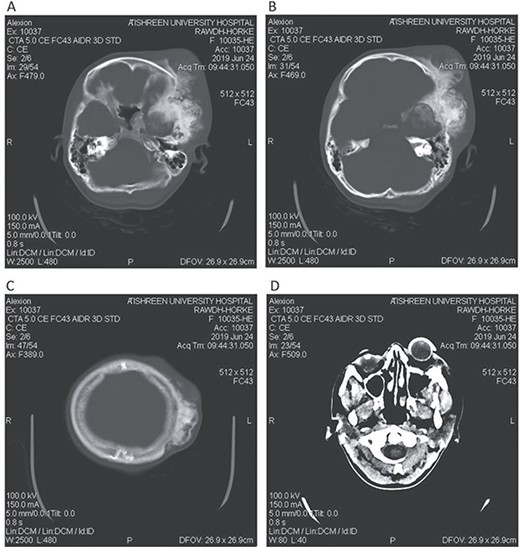

CT head tissue window (A, B). A. Invasion of the maxillary sinus and orbit. B. Invasion of the parietal, temporal and frontal lobes. A remarkable exophthalmos. Bone window (C, D). C. The bone-forming lesion showing the same density of the bone. D. Invasion of the sphenoid, temporal and parietal bones.

A 17-year-old female presented with a history of osteosarcoma that was confirmed after undergoing a surgery to remove an enlarging bone tumor in the left temporal region 2 years ago. She later got pregnant and delivered her child but never got back for a checkup until she was admitted to our hospital with a severe and unresponsive to medication headache that progressed over the course of 6 months and blurred vision that progressed to complete left-sided vision loss. Physical examination revealed a tough and mobile yet fixed at the base 7-cm mass towards the left of the frontal bone. Many more masses were revealed in the left side of the skull including the anterior cranial fossa, orbit, base of the skull and the left part of the occipital region where the previous procedure was performed (Fig. 1). These masses had been increasing in size probably under the influence of pregnancy hormones causing pain that radiated along the orbital and maxillary branches of the left trigeminal nerve. Physical examination and past medical history were otherwise unremarkable. Laboratory tests were all normal, and her family history was negative. Staging studies showed no evidence of distant metastatic disease in the chest, the abdomen and the pelvis. CT scan of the skull revealed a bone-forming non-lytic lesion accompanied by periosteal reaction. This lesion bulges to the outside towards the scalp spreading into both the soft tissues and the inside of the entire left side of the skull with a sunburst-pattern (Figs 2 and 3). Its rims are unsymmetrical and pointy, and it bulges into the left orbit outside the muscles causing exophthalmos with a semi-complete proptosis of the eyeball out of the orbit (Figs 2 and 3). This lesion applies pressure to the left frontal and temporal lobes causing mild edema in both these lobes without invading the brain tissue. This edema in turn applies pressure to the left lateral ventricles (minor shift of the elements of the midline to the right side can be seen on CT) (Fig. 4). Due to the tumor’s wide spread, the surgical procedure was performed in two stages (approximately 6-hour-long each). In the first stage, the bone mass was removed through a procedure of wide skull approach including the frontal, temporal and parietal bones and a removal of the invading part of the temporal muscle. Moreover, the lateral wall and roof of the left orbit were removed, the left optic nerve was dissected free and part of the meninges was removed and replaced with an autogenic patch from the fascia lata. Then, the bone loss was compensated for by using bone cement Synicem VTP (poly methyl methacrylate and Barium sulfate), and the orbit was rebuilt; the eyeball was placed back with noticeable decline of the exophthalmos. In the second stage, a complementary left parietal occipital incision of the previous approach was performed 3 weeks later; the remaining of the frontal and occipital bones was removed, and a partial mastoid surgery was done. Furthermore, the cavernous sinus were revealed and found to be not invaded. Later on, the normal skull shape was restored using the same cement. The histopathology of the lesion revealed proliferation of neoplastic chondroblasts, osteoblasts and spindle-shaped cells. The features are consistent with low-grade chondroblastic osteosarcoma (Fig. 5). The patient did not need ICU admission. She recovered well 3 days after the surgery and was discharged with no deficits. A CT scan that was performed post-operatively revealed that the masses were successfully excised (Figs 6 and 7). At the last follow-up 1 month post-operation, the patient was scheduled to undergo a course of radiotherapy, 60 Gy of radiotherapy in 30 fractions over 4 weeks without chemotherapy, as it is not recommended with low-grade osteosarcoma.